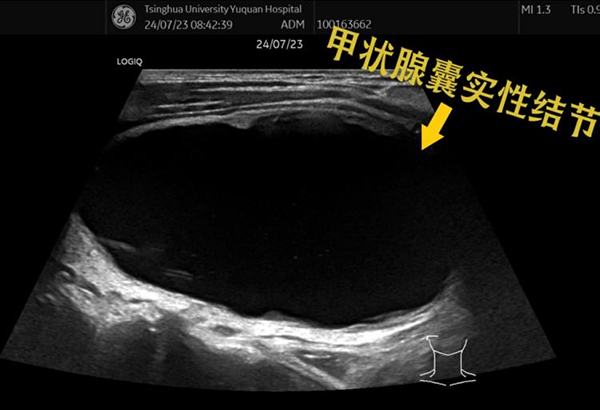

近期,一位来自河北保定的中年男性患者,通过了解超声诊断科卜云芸主任团队的科普视频,来我院就诊。该患者自述2年前因为生气,脖子上突然长出一个大包,去医院检查发现甲状腺内有一个囊实性结节,大小约2cm左右,一直未在意,直到现在结节越长越大,已经有明显的压迫感,并且影响吞咽和呼吸,于是四处求医,先后在当地市医院、北京其他三甲医院进行了对比、斟酌,最后决定来我院就诊。

卜云芸主任团队为该患者进行了详细的术前评估,这是一个以囊性为主的囊实性结节,最大直径已达7.3cm,在充分告知患者手术切除和超声引导下微创消融各自的优缺点后,患者主动选择超声引导下微创消融治疗。

消融前